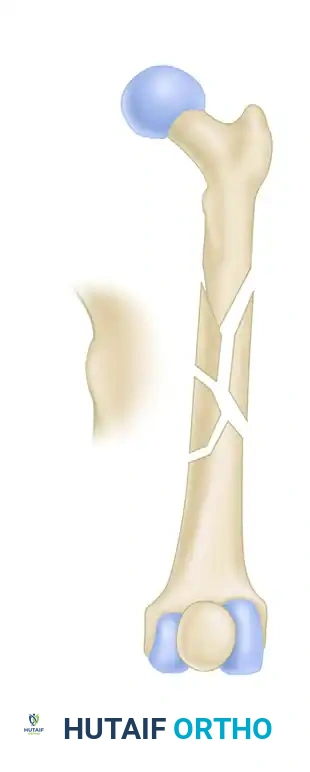

FIGURE 55-48: Proximal femoral locking plate fixation of a subtrochanteric femoral fracture with proximal extension. (A) Preoperative radiograph. (B) Preoperative axial CT scan shows extension proximally into the piriformis fossa. (C and D) Postoperative AP and lateral radiographs after fixation with a locking plate.

FIGURE 55-49: Fixation of a subtrochanteric nonunion with a blade plate. (A) Preoperative radiograph demonstrating hypertrophic nonunion. (B and C) Postoperative radiographs after rigid fixation and compression with a blade plate.